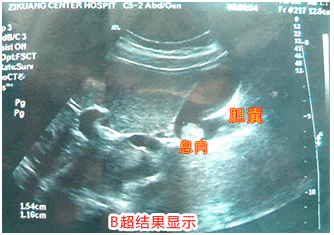

细分为肾结石、尿道结石、输尿管结石、膀胱结石、胆结石、胆总管结石、肝内胆管结石、胆囊息肉等8大结石诊疗项目,真正做到:专病专医专治,提高诊疗效率,让患者安心、舒心、放心。